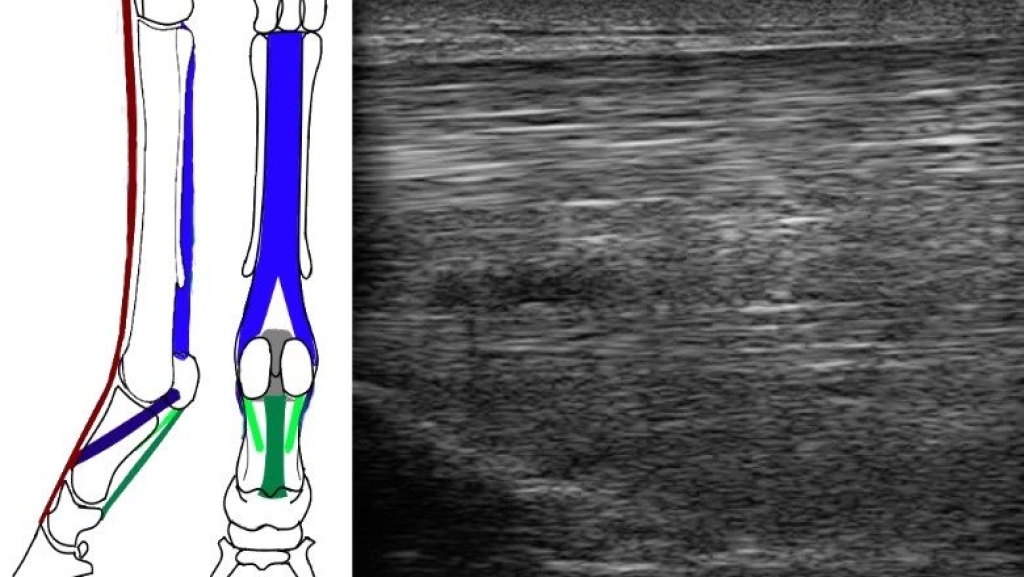

We hebben weer een informatief artikel over tussenpeesblessures geschreven, deze is te lezen op paardenarts.